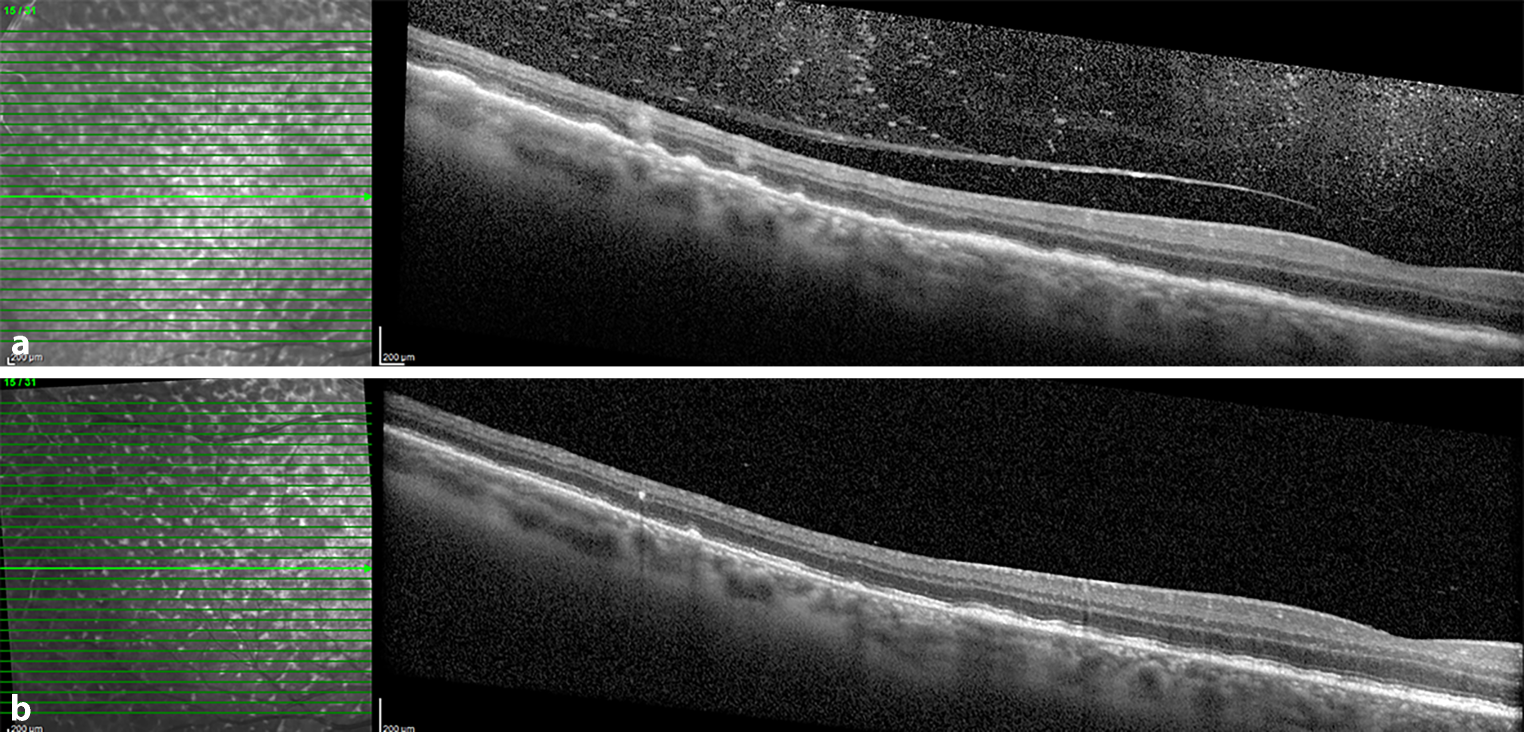

Bildgebende Verfahren, insbesondere die optische Kohärenztomographie (OCT), können sehr hilfreich sein, um den Verdacht auf VRL abzuklären [14]. In einer aktuellen retrospektiven Fallserie von 182 Augen von PatientInnen mit histologisch bestätigter VRL fanden Pichi et al. eine Infiltration des subretinalen Pigmentepithels in 91 %, des subretinalen Kompartiments in 43 % und des intraretinalen Kompartiments in 7 % der Augen [15]. Es ist wichtig zu erwähnen, dass alle OCT-Veränderungen beim VRL oberhalb der Bruch-Membran liegen. Obwohl viele der beobachteten OCT-Veränderungen der Morphologie anderer Krankheitsentitäten sehr ähnlich sind, können einige OCT-Merkmale als pathognomonisch für das VRL bezeichnet werden. Dazu gehören die „cloudy“ vitelliformen Läsionen im subretinalen Raum und die vertikalen hyperreflektiven Läsionen in der Neuroretina (Abb. 1 und 2; [16, 17]). Ein weiteres interessantes, wenn auch nicht ganz zuverlässiges Merkmal der OCT ist das Fehlen eines zystoiden Makulaödems bei VRL. Allerdings wurden Makulaödeme bei VRL nach vorangegangener Augenoperation und selten auch ohne vorangegangene Operation beschrieben [18].

Abb. 1

Optische Kohärenztomographie(OCT)-Bilder der temporalen Netzhaut eines PatientInnen mit vitreoretinalem Lymphom (VRL). a Die erste OCT bei Diagnosestellung zeigt eine große Anzahl hyperreflektiver Foci im Glaskörper, ein unregelmäßiges RPE mit flachen RPE-Ablösungen und Material zwischen RPE und Bruch-Membran sowie zwei säulenförmige hyperreflektive Läsionen in der Neuroretina (vertikale hyperreflektive Läsionen). b Nach 3 intravitrealen Methotrexatinjektionen sind die vertikalen hyperreflektiven Läsionen fast verschwunden, sodass nur noch ein kleiner hyperreflektiver Punkt vorhanden ist, die Glaskörperinfiltrate sind verschwunden, und die PED haben sich zurückgebildet, sodass nur noch wenige RPE-Unregelmäßigkeiten vorhanden sind